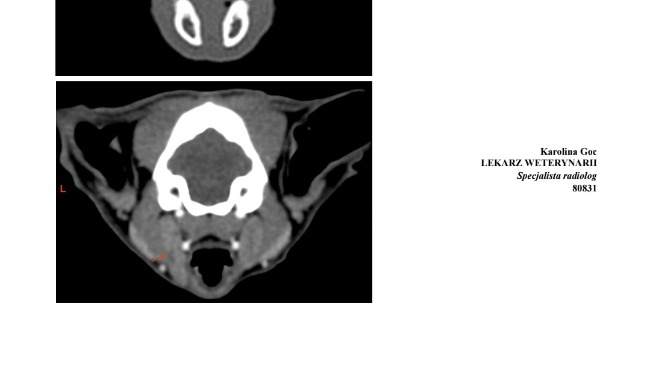

Wyniki tomografii głowy pokazują, jak bardzo choroba niszczy jej organizm:

• przewlekłe zapalenie jam nosowych z ropnym wysiękiem,

• zatkane przewody nosa i zatok, które utrudniają oddychanie,

• ubytki w przegrodzie nosowej,

• zanik kostny małżowin nosowych,

• powiększone węzły chłonne świadczące o ciągłej walce z infekcją.